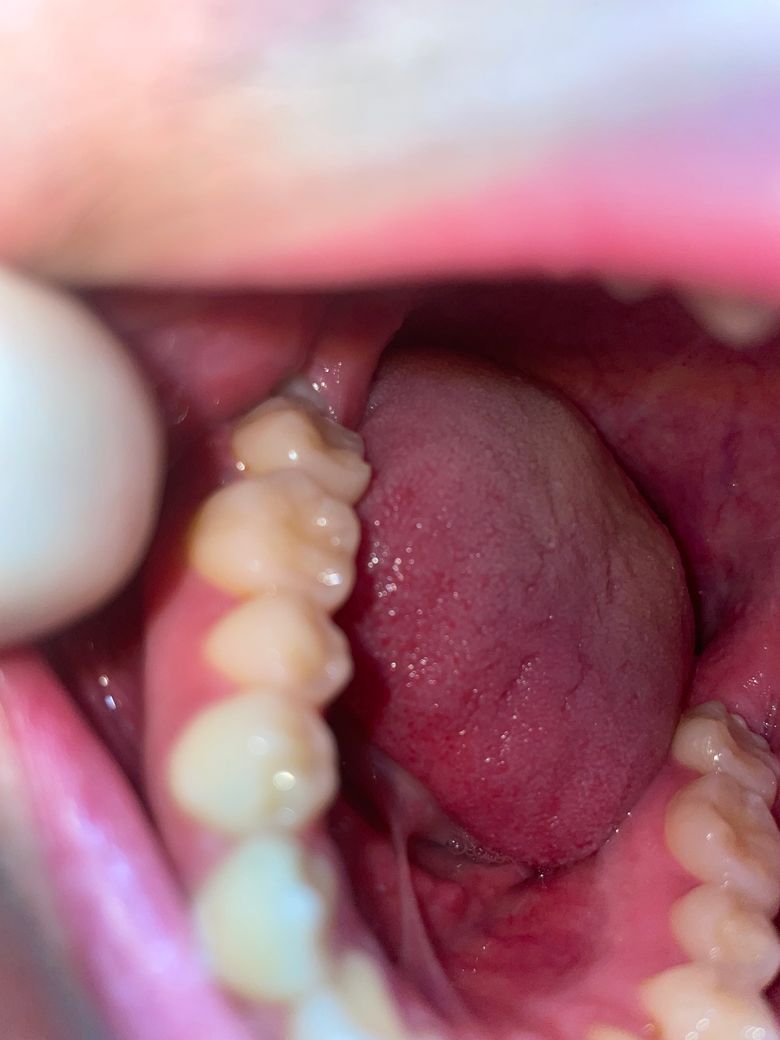

어금니 잇몸이 부었는데 이거 치과 빨리 가봐야 하나요?

왼쪽 어금니 옆쪽에 조금 부었어요 예전에도 부었다가 다시 가라앉았는데 지금은 노란빛도 좀 보이는데 이거 고름인가요..?? ㅠㅠㅠㅠ 돈도 없는데 어떡하죠..치료하면 많이 아플까요 당장 치과 가봐야 할까요 양치할때 피는 안나고 저기서도 피는 안나요 딱히 아프지도 않고 조금의 이물감만 존재합니다

사랑니때문에 그런거 같으니 불편하시면 치과에 가셔서 잇몸치료를 먼저 받아보시면될것같습니다.

사진으로는 정확한 확인이 어려워 보입니다 사랑니가 부분적으로 맹출되어 있을 경우에는 해당 부위에 음식물이 끼기 때문에 쉽게 염증이 생길 수 있습니다.

사랑의 주변에 염증이 자주 생긴다면 발치를 해 주는 것이 좋을 수 있습니다.

오른쪽 아래 어금니 부위 부종이 관찰되며 부분매복 사랑니로 인한 치관주위염도 예상됩니다. 일단 치과에서 스케일링과 잇몸치료를 받으시고 사랑니도 발치하는 방향으로 진행해보시기 바랍니다.